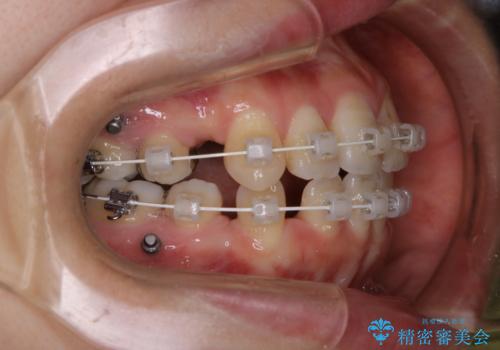

- ワイヤー矯正中のメンテナンスでPMTCを希望されました。染め出しを行い、歯ブラシ指導とPMTC30分コースを行いました。

毎日しっかりと磨いているようでも、装置の周りや歯と歯の間・歯と歯茎の間に磨き残しが残ってしまいます。そのため磨き残しをチェックする『染め出し剤』を使用すると明確に磨き残しを見ることができます。

染め出されている部分の磨き残しは、毎日の習慣として歯ブラシをしていてもいつも磨けてない部分です。